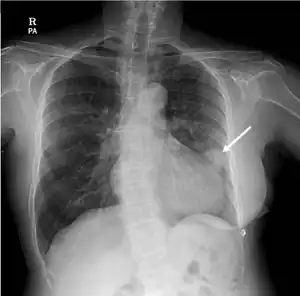

| Rounded, bulging mass in the superior cardiac border and adjacent lung nodule arrow on chest X-ray. | |

Tuberculous pericarditis is a form of pericarditis.